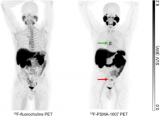

用于前列腺癌的PET示踪剂在III期试验中表现良好

根据发表在《核医学杂志》4月刊上的一篇临床结果报告显示,使用F-18 PSMA-1007的PET/CT成像比使用标准F-18 fluorocholine (FCH)放射性示踪剂的成像检测到更多的前列腺癌。